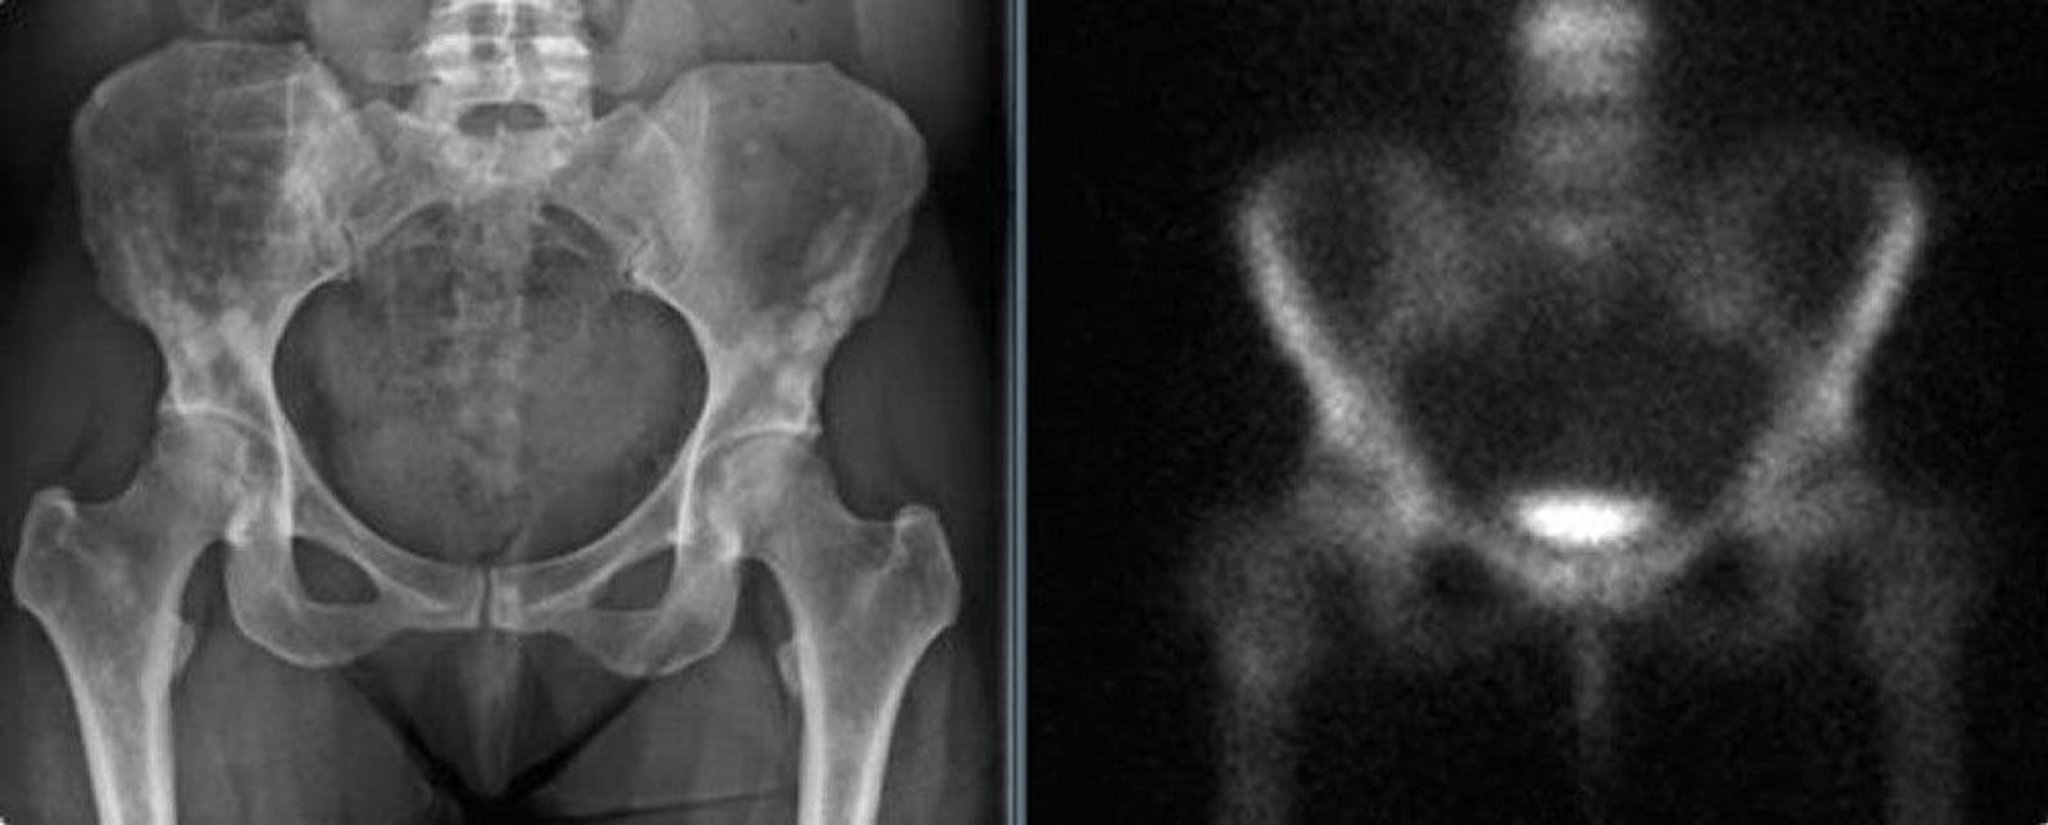

骨盤の骨斑紋症

55歳女性の骨盤に生じた骨斑紋症のX線写真(転倒の可能性があった後に撮影)であり,陰影が乳房の造骨性転移と間違えられる可能性がある(左)。骨シンチグラフィーでは有意な集積亢進を認めない(右)。

Images courtesy of Michael J.Joyce, MD, and David M.Joyce, MD.